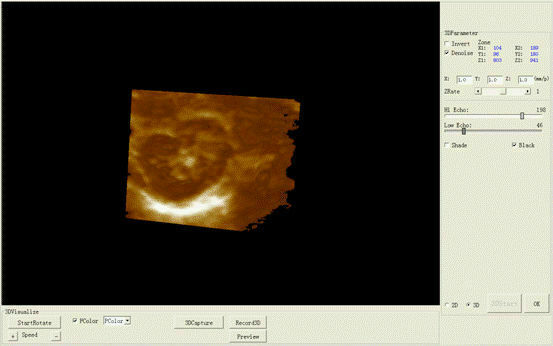

Designed with portability and functionality in mind, the New Portable Notebook Digital Laptop Machine offers superior performance without compromising on ease of use. Its compact size allows for easy transport and setup, while the digital laptop interface ensures that users can quickly access and utilize the scanner's capabilities. The inclusion of a convex probe and 3D imaging further enhances the diagnostic accuracy, providing clearer and more detailed images than ever before.

In addition to its user-friendly design, the New Portable Notebook Digital Laptop Machine provides high-resolution imaging that is crucial for accurate diagnostics. The 3D imaging capability allows for more comprehensive assessments of anatomical structures, leading to better treatment planning and patient management. Whether used for routine check-ups or complex medical evaluations, this ultrasound scanner delivers reliable and precise results.

Overall, the New Portable Notebook Digital Laptop Machine with Ultrasound Scanner and Convex Probe+3D is a state-of-the-art tool that embodies innovation, portability, and efficiency. It empowers medical professionals to provide high-quality care in various scenarios and enhances the overall diagnostic process. Investing in this advanced ultrasound machine is a step towards improving patient outcomes and expanding the capabilities of ultrasound imaging in modern medicine.